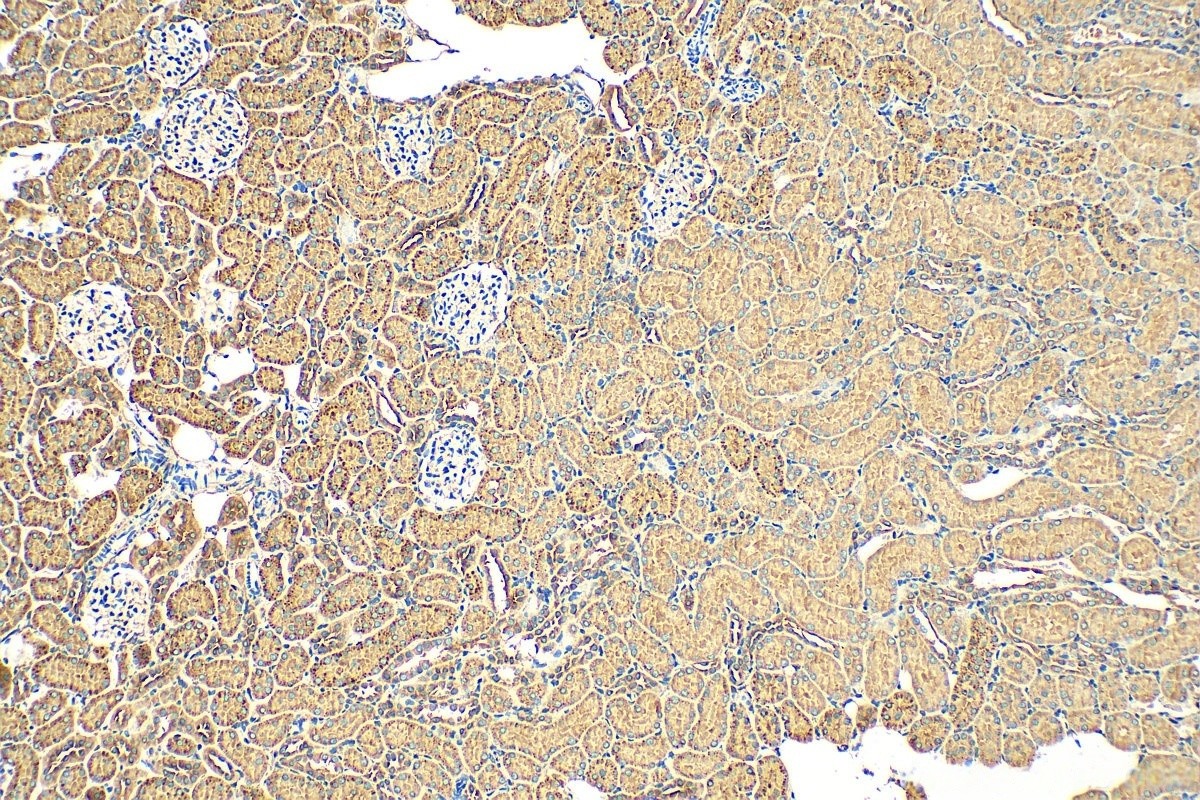

Immunohistochemical analysis of paraffin-embedded human kidney tissue slide using (TXNIP Antibody) at dilution of 1:200 (under 10x lens).

Immunohistochemical analysis of paraffin-embedded human kidney tissue slide using (TXNIP Antibody) at dilution of 1:200 (under 40x lens).